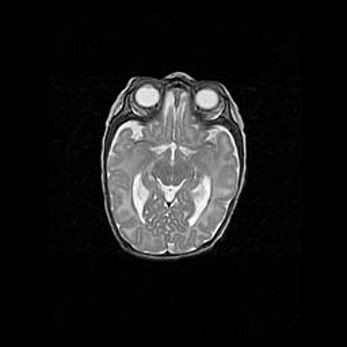

Открытая гидроцефалия.

Возраст: 9 месяцев 12 дней

Вес: 6800 г

Пол: мужской

Окружность головы: 41,5 см

Срок гестации: 28 недель

Гидроцефалия головного мозга у новорожденных имеет характерный признак: опережающий рост окружности головы приводит к визуально хорошо определяемой гидроцефальной форме сильно увеличенного в объёме черепа. Детские неврологи определяют следующие симптомы гидроцефалии у грудничков: выбухающий напряжённый родничок, частое запрокидывание головы, смещение глазных яблок к низу.